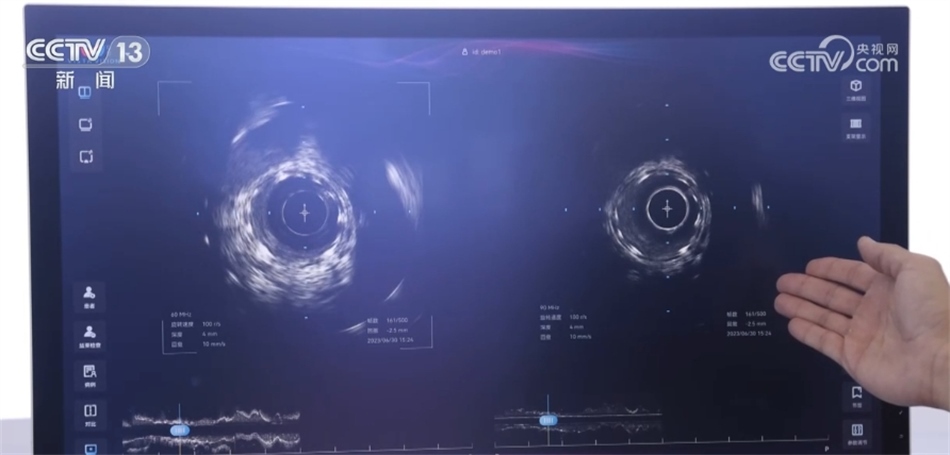

總臺央視記者 褚爾嘉:這里是一個傳統(tǒng)的血管的超聲圖像,我們可以看到血管的全貌。右邊這里是一個工作頻率高達(dá)100兆赫茲的超高頻的血管內(nèi)超聲圖像,通過技術(shù)升級,現(xiàn)在我們可以更加清晰地看到冠狀動脈的精細(xì)結(jié)構(gòu),這也是目前世界上清晰度最高的一個血管內(nèi)的超聲圖像。

中國科學(xué)院深圳先進(jìn)技術(shù)研究院研究員 馬騰:在醫(yī)學(xué)影像領(lǐng)域,圖像的分辨率和深度是不可兼得的。我們創(chuàng)新性地將一個超高頻的探頭和一個傳統(tǒng)的探頭融入到一個導(dǎo)管里,在不改變導(dǎo)管尺寸的情況下,可以為醫(yī)生提供一個大深度、高精度二者兼得的圖像。對于一些冠狀動脈急性病癥,包括斑塊的診斷以及介入手術(shù)的治療,會給醫(yī)生提供一個更加全面、更加有效的醫(yī)療影像學(xué)工具。